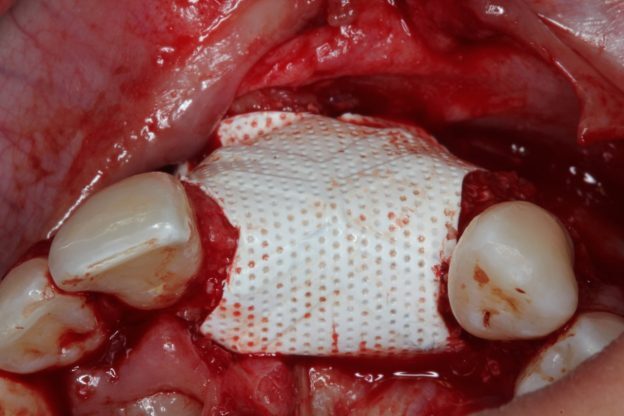

Extraction Socket – Preservation/Grafting; Immediate vs Delayed Implants; Pontic Site Development